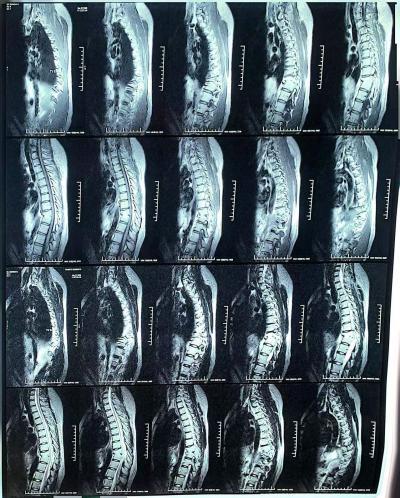

接诊后,医疗队骨科副主任医师黄先哲、放射科主治医师陈娟、中医药中心副主任医师周胜强共同联合会诊,全面排除结核、骨折等病症,最终确诊患者为D10 半椎体畸形、D9‑D11 椎体发育不全伴局部后凸畸形,继发周围软组织慢性炎症。经周胜强副主任医师细致体格检查与中医详细辨证,决定采用调衡针灸为其治疗。